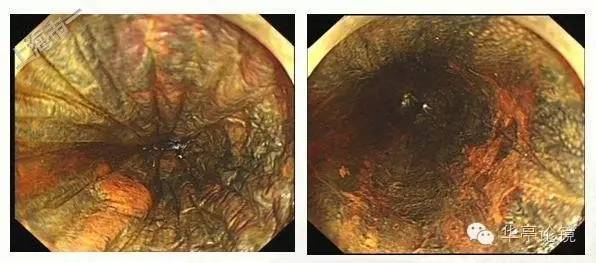

白光内镜:可见距门齿25-29cm见多片浅表糜烂,局部粘膜发白、呈粗糙不平或局部伴凹陷, 黏膜血管网紊乱或缺失。EUS提示:病变处粘膜增厚,见低回声改变,粘膜下层完整。未见周围肿大淋巴结,见下图。

卢戈氏碘染色:病变区多片不染区,形态不规则,见下图。

ME-NBI内镜:见多处病灶粘膜血管网异常,分支血管网缺失,局部背景着色阳性,IPCL呈IV-V1型改变为主(注:IV型: 出现扩张、迂曲、管径粗细不均或形态不规则改变中的2种或3种;V型:同时出现扩张、迂曲、管径粗细不均和形态不规则四种改变),局部见V2型改变(注:Ⅴ2型:在Ⅴ1型病变的基础上出现血管延长,原血管袢结构尚完整)。预测病变深度为m1(上皮层)为主,见下图。本文IPCL分型均按井上分型方法。